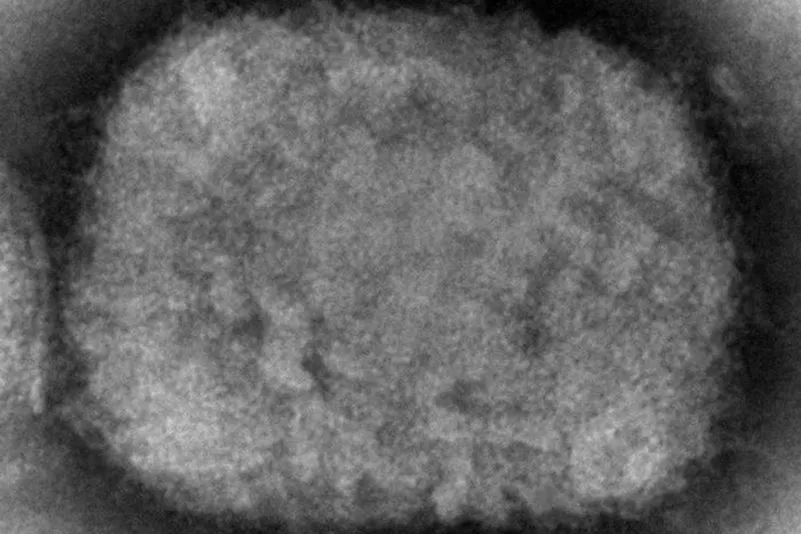

Die Aidshilfe spricht sich im Umgang mit Affenpocken gegen Stigmatisierung aus.

Foto: Cynthia S. Goldsmith/CDC via AP/dpa